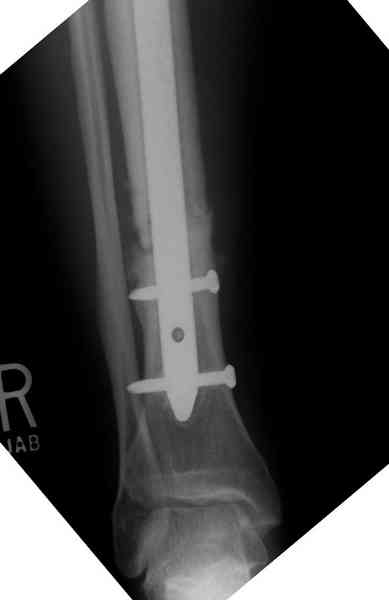

Нет. Просвет внутри кейджа - 13 мм, штифт - 12 мм. Не так там и много пространства то есть. Но вопрос правильный, интересный, из разряда современных нерешенных проблем.

The cages are commercially available but up to 10 cm. So we measured the needed length on x-rays, added 2 cm at both ends for sure that

the resected piece will include all, and resulted with 15 cm which one was ordered and individually made by the same factory. So yes, we made the gap to fit the cage.

The inner diameter of the tube is 13 mm, the nail was 12 mm, so not so much space to put something inside. Yes, this is really shaft endoprosthesis which i hardly ever would offer for a young football player. Though... Maybe we would when we collect some experience with this sort of implants to feel/prognose its strength in different settings.